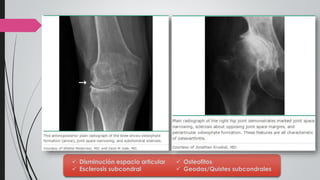

Rx de pelvis AP y caderas en abducción

+/-

Rx de rodillas de pie AP y lateral (en

carga) y axial de rótulas

 Disminución espacio articular

 Esclerosis subcondral

 Osteofitos

 Geodas/Quistes subcondrales